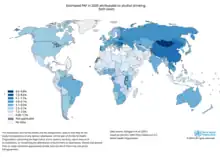

United States

In the United States of America, alcohol-related cancer rates were highest in the following states: Delaware, Colorado, the Washington, D.C., New Hampshire, and Alaska.[9] Conversely, alcohol-related cancer rates were lowest in the following states: Kentucky, Arizona, Oklahoma, West Virginia, and Utah.[9]

From 2013 to 2016, approximately 19,000 (4%) cancer-related deaths in the United States were attributed to alcohol consumption each year, with breast cancer and esophageal cancer deaths being the most common in women and men respectively.[10][11]

An estimated 3.2% of cancer deaths in United States were attributed to alcohol consumption. The distribution of mortality by state were consistent with the distribution of incident cases.[9]

Europe

Approximately 10% and 3% of cancer diagnoses in European men and women respectively are attributed to alcohol consumption.[12]

Europe: A 2011 study found that one in 10 of all cancers in men and one in 33 in women were caused by past or current alcohol intake.[13][14]

Australia

Australia: A 2009 study found that 2,100 Australians die from alcohol-related cancer each year.[15]